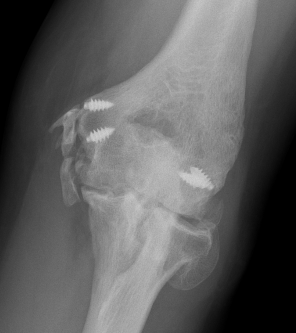

Xray

Radio-ulna synostosis

CT

Define anatomical location of the HO prior to surgical excision